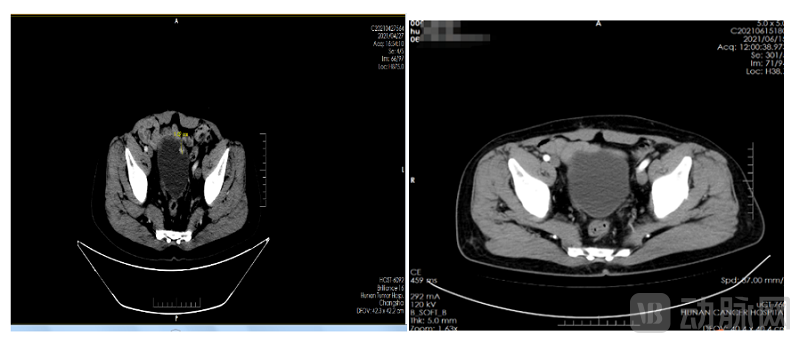

后入组MRG002 治疗经至少一线全身化疗的HER2阳性无法手术切除的局部晚期或转移性尿路上皮癌的开放、单臂、多中心 II 期临床试验,接受MRG002单药治疗,经过2周期治疗后其中非靶病灶全部消失,一个靶病灶消失,另一个靶病灶腹膜后淋巴结缩小至6.5mm,具体见下图:

图2. 腹膜后淋巴结基线(左)和首次用药后6周腹膜后淋巴结(右)